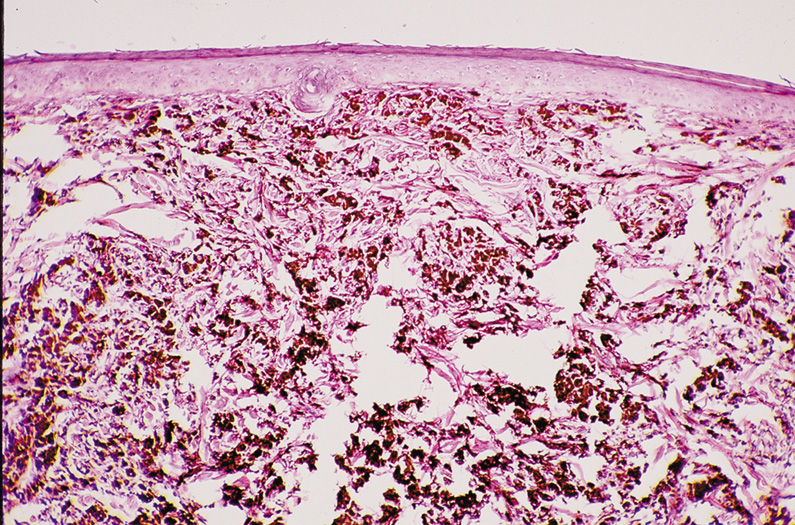

Umbilicated vesicles on an erythematous base progressing to pustules and crusted papules are characteristic of generalized vaccinia (small pox), with new cases recently reported secondary to the small pox vaccine. These vesicles are also characteristic of varicella (chickenpox), herpes zoster (shingles), and primary and recurrent herpes simplex infections (Fig. 6A). Herpesviruses are DNA-containing viruses that infect host cell nuclei resulting in similar, characteristic histologic changes. There is marked intraepidermal vesiculation and necrosis with massive ballooning and rupture of keratinocytes, spongiosis, acantholysis, and a dense superficial dermal perivascular lymphohistiocytic infiltrate with neutrophils, which also are seen commonly infiltrating the epidermis. Multinucleated epithelial giant cells with nuclei, which are steel gray and demonstrate peripheral margination of clumped chromatin material, are characteristic of early and well-developed vesicles (see Fig. 6B). Progression to near total epidermal necrosis makes these characteristic cells more difficult to identify. Occasionally, eosinophilic staining and small intranuclear inclusions may be visible. A Tzanck smear may be obtained by unroofing a vesicle, scraping the base, and staining the base with Giemsa stain. This rapid diagnostic method enables identification of multinucleated epithelial giant cells and single keratinocytes with characteristic nuclear changes.

Fig. 6. A. Recurrent herpes simplex infection with umbilicated pustulovesicles on an erythematous base. B. Herpes simplex infection with intraepidermal vesicle containing characteristic multinucleated epithelial giant cells.